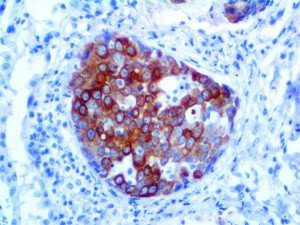

It is the ICU physician who is most likely to witness one of the deadliest manifestations of the abnormal immunological response, the cytokine storm syndrome (CSS). This response is also referred to by some as the cytokine release syndrome (CRS). CSS is characterized by continuous activation and expansion of macrophage and lymphocyte populations, which secrete large amounts of cytokines, causing the cytokine storm. This massive cytokine release is akin to hemophagocytic lymphohistiocytosis (HLH) disease, a syndrome characterized by initial unchecked and persistent activation of cytotoxic T lymphocytes and NK cells.

Clinical and laboratory manifestations of HLH include fever, enlarged liver and/or spleen, neurologic dysfunction, coagulopathy, liver dysfunction, cytopenias (i.e., low levels of erythrocytes, leukocytes, and/or platelets), hypertriglyceridemia, hyperferritinemia, hemophagocytosis, and eventually diminished NK cell activity as the immune system becomes progressively paralyzed. HLH can be familial (primary HLH) or secondary to another disease process (sHLH), such as rheumatic disease, in which it is referred to as macrophage activation syndrome (MAS, characterized by elevated ferritin).

This activation induces inflammatory monocytes to highly express IL-6, starting a localized and then systemic cascade effect that results in hyperproduction of IL-6, which accelerates the inflammatory process. Because IL-6 also increases vascular permeability, excessive levels cause blood vessels to become very leaky. This, along with clotting factors released from vascular endothelial cells, stimulates the coagulation cascade, resulting in microthrombosis (tiny clots), which leads to ischemia and tissue death of the kidney, intestines, heart, liver, brain and extremities.